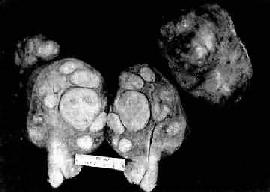

图13-7 子宫平滑肌瘤 多个肌瘤结节,位于肌壁内、粘膜下及浆膜下,境界分明,宫腔受挤压呈裂隙状 镜下,瘤细胞与正常子宫平滑肌细胞相似,但肌瘤细胞核比较密集,常排列成纵横交错的不规则束状或成编织状。核大多呈长杆状、两端钝圆或圆锥形,染色质纤细。肌细胞间有不等量的结缔组织。每10个高倍(400倍)视野核分裂像少于5个者一般为良性。有少数病例瘤细胞核增多、致密,核大活跃,染色质粗,无核分裂像,称细胞性平滑肌瘤(cellular leiomyoma)。子宫平滑肌瘤的恶变率很低,据报道为0.2%~0.5%,多见于年龄较大、生长较快与较大的肌瘤。如果核分裂像每个高倍视野达10个以上或有肌层及血管浸润者应诊断平滑肌肉瘤。 (二)子宫体癌 子宫体癌又称子宫内膜癌(carcinoma of endometrium),较常见,占女性生殖道恶性肿瘤的20%~30%。近年来子宫体癌的发病率有上升趋势。多发生在50岁以上绝经期和绝经期后妇女。病因未明,一般认为与雌激素长期持续作用有关。主要临床表现为不规则阴道流血。 【病变】 肉眼观,分弥漫型及局限型两种。弥漫型的子宫内膜呈弥漫增厚,不规则形、息肉或菜花状,质脆,常见出血、坏死或溃疡形成。癌组织浸润肌层,深浅不一(图13-8)。局限型多位于宫底或宫角,后壁多于前壁,常呈息肉状伴肌层浸润。

图13-8 子宫体腺癌(弥漫型) 癌组织弥漫浸润子宫壁,且部分突入子宫腔中形成大不不等的乳头状肿块 镜下,子宫内膜癌多数为分化较好的腺癌。腺体数目增多,形状和大小不一,排列紊乱,腺体呈“背靠背”形式。腺体由单层或复层细胞组成,形成条索状“搭桥”。间质极少。有时腺上皮增生形成实体性癌巢。癌细胞呈柱状或多角形,可有不同程度的分化。胞浆中等量,淡染;核大小不一,染色质增多而深染,核仁明显,可有正常或病理核分裂像。根据分化程度,子宫内膜癌可分为3级:Ⅰ级(高分化腺癌),腺体较规则,同单层细胞组成,细胞排列紧密有的成假复层或复层。核分裂像少见(图13-9)。Ⅱ型(中分化腺癌),腺体不规则,有较多腺样结构或小腺体形成,可有少量实性区。癌细胞分化较差,核分裂像易见。Ⅲ级(低分化腺癌),腺体结构极少见,癌巢多呈实性片块状,细胞异型性明显,核分裂像多见。有些腺癌组织中可见良性化生的鳞状上皮团,称腺棘癌(adenoacanthoma)。如果腺癌内混有恶性鳞状上皮,称腺鳞癌(adenosquamous carcinoma),多见于分化较差的腺癌。少数子宫内膜癌含有透明细胞,或含粘液的细胞。有些可形成乳头状子宫内膜癌。